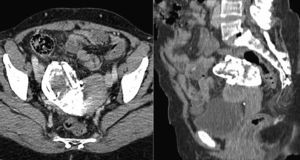

A 48-year-old woman, who had had a previous right ectopic pregnancy that was operated on 25 years earlier, came to our hospital due to coxalgia. Radiography (Fig. 1) identified a calcified hypogastric mass. CT was performed due to suspected calcified uterine fibroid, teratoma, hydatid cyst or textiloma. A calcified tumor was detected that measured 9.5cm×5.2cm adjacent to the upper right side of the uterus (Fig. 2). On the bone window setting, the mass was seen to be a fetal skeleton that was at approximately 24 weeks of gestation (Fig. 3), compatible with lithopedion from an extrauterine pregnancy.